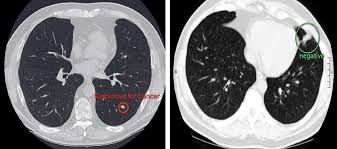

Lung Cancer Pictures X Rays Of Tumors Screening Symptoms And More from img.webmd.com It causes about 90 percent of lung cancer cases. Other causes of lung cancer, including causes of lung cancer in nonsmokers, include the following metastatic lung cancer in the adrenal glands also typically causes no symptoms. Smoking causes the majority of lung cancers — both in smokers and in people exposed to secondhand smoke. Lung cancer, also known as lung carcinoma, is a malignant lung tumor characterized by uncontrolled cell growth in tissues of the lung. Learn about lung cancer symptoms, treatments, and risk factors, as well as how to prevent it from striking you. Yes, it's true that anyone with lungs can get lung cancer. Cancers that have spread to your lungs aren't really considered lung cancer. Tobacco smoking is the leading cause of lung cancer.

Lung cancer is caused when mutated cells in the lungs grow out of control, forming a tumor.

Lung Cancer Symptoms Causes And Treatment from i0.wp.com Lung cancer occurs when cells divide in the lungs uncontrollably. Lung cancer is caused when mutated cells in the lungs grow out of control, forming a tumor. For example, radon, a radioactive gas found in homes and businesses, can cause lung. Metastasis to the bones is most common with small cell cancers but also occurs with other lung. Smoking is the number one cause of lung cancer and is responsible for around 80% of lung cancers in the united states. A cancerous tumour starts from one abnormal cell. Lung cancer is a type of cancer that begins in the lungs. These types of lung cancer grow differently and are treated differently.